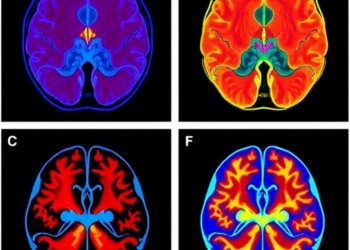

Neuromorphic Event-Based Camera Achieves Kilohertz Vascular Imaging and Functional Brain Reconstruction in Living Subjects

In a groundbreaking leap for neurophotonics and biomedical imaging, researchers from South Korea and the United States have unveiled a ...